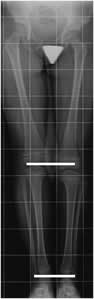

Fig 104 B. Acortamiento.

Rx AP. Acortamiento de la extremidad izquierda, a expensas del fémur por fractura antigua y consolidada del tercio distal.